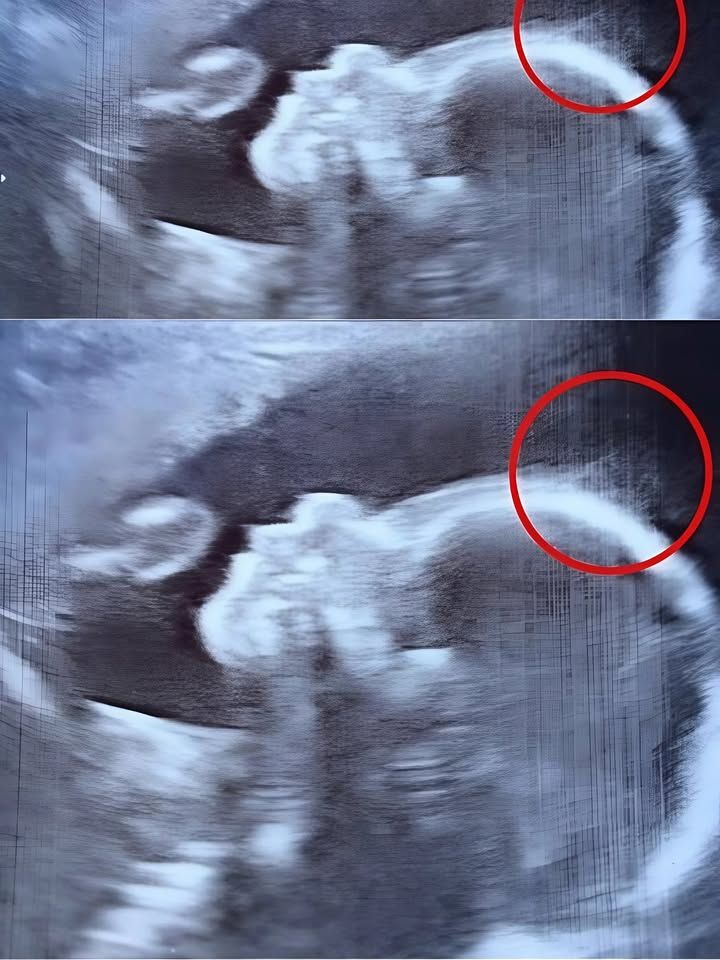

Het echografieonderzoek toonde inderdaad dunne sliertjes die onder water heen en weer bewogen als zeewier.